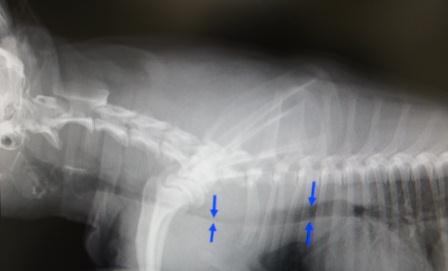

ワンちゃんの胸の側面からのレントゲン写真です。 矢印で示される黒く抜けた部分が気管です。 正常であれば気管の幅は常に一定です。 しかし、このワンちゃんは左側の矢印で示される部分の 幅が右側より細くなり、気管が変形していることが分かります。 |